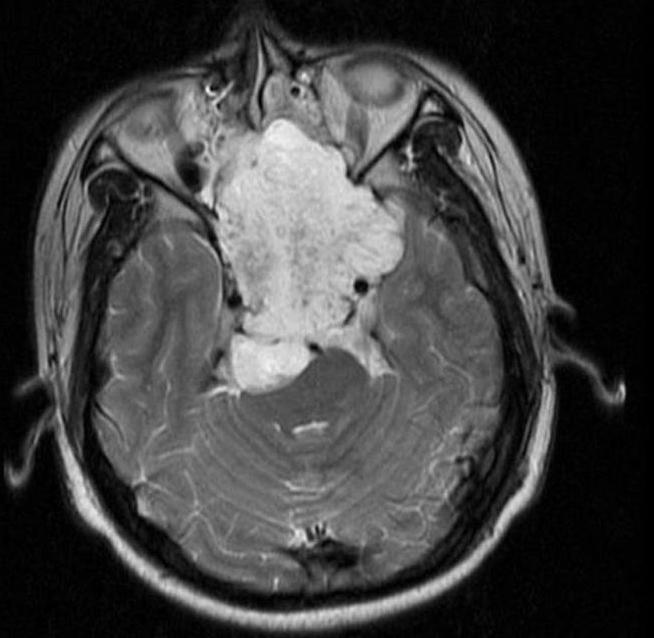

Resonancia Magnética (RM)

Es la técnica de imagen más importante y definitiva.

- Señal: Hipointensa en T1 (a menos que haya hemorragia), hiperintensa en T2 (por su alto contenido acuoso/mixoide).

- Realce: Se realza de forma heterogénea e intensa con contraste (gadolinio).

- Utilidad: Define con precisión la extensión intramedular, el componente de partes blandas, la relación con estructuras neurovasculares críticas (médula, raíces, vasos, vísceras) y la respuesta al tratamiento.